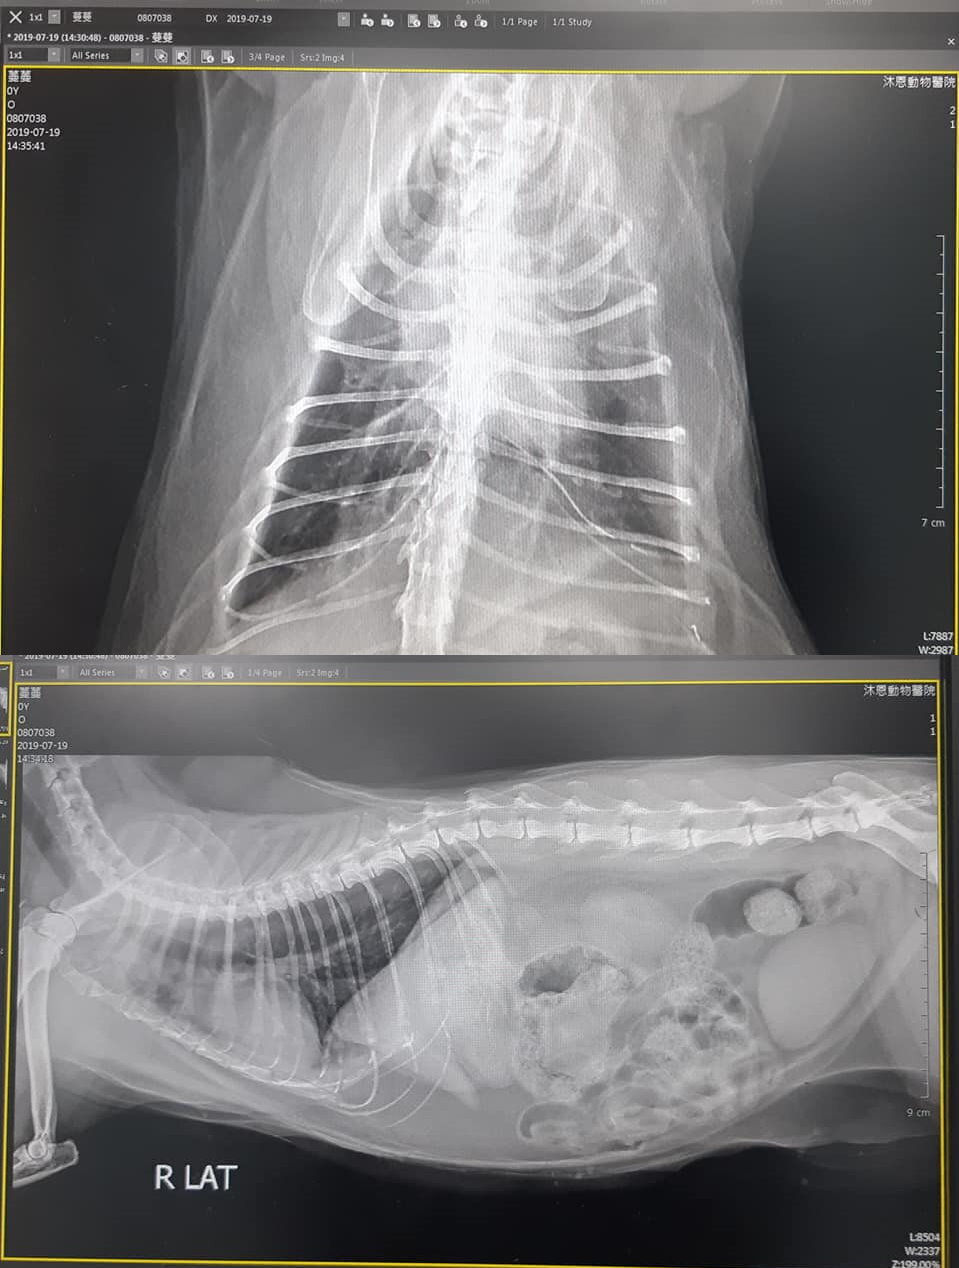

這是7/19 蔓蔓 沐恩看診的情況:

3. X光檢查,心臟無發現異常,肺後葉血管較粗,此情況通常是腎或心肺問題引起,醫師認為較可能是心肺方面問題,但因聽診檢查無雜音,再請留意蔓蔓有無咳嗽、張嘴呼吸。

沐恩7/19看診血檢、X光、尿檢和口服藥5000元